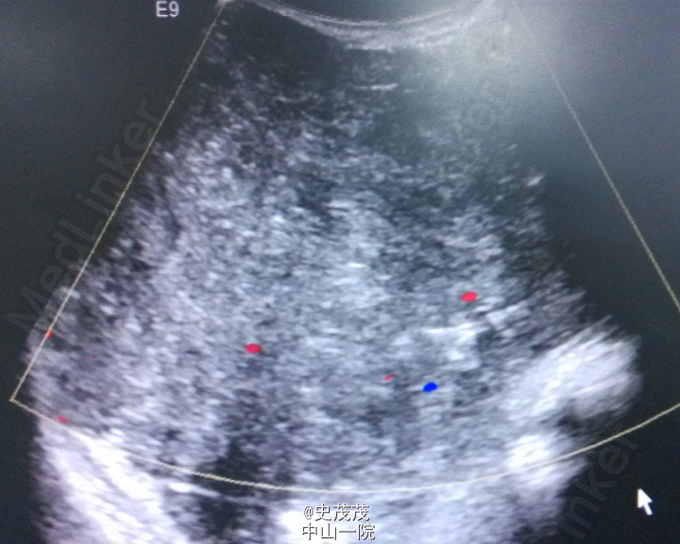

47岁,女性,因“发现右乳肿物2年余”入院。患者于2年前无明显诱因发现右乳肿物,局部哟红肿、疼痛不适,乳头无异常溢血溢液,肿物于月经来潮前疼痛加剧。半年来肿物逐渐增大,伴疼痛。既往史:2年前因“右侧乳房巨大乳腺纤维瘤”行纤维瘤切除术。查体:双侧乳房对称,皮肤未见桔皮征及酒窝征,乳头无凹陷、畸形。右乳外上象限可及一约20cm×10cm大小肿物,质中,表面光滑,边界清,活动度可,无压痛,与皮肤无黏连。挤压乳头无溢血、溢液。同侧腋窝及锁骨淋巴结均未及明显异常。对侧乳房未及异常。辅助检查:乳腺B超:1、右侧乳房局灶性病变,位于全乳腺体层,范围210×100mm,呈低混合回声,境界清晰,呈膨胀式生长。彩色血流检查瘤体内部见丰富血流信号,考虑叶状囊肉瘤,符BI-RADS 5 级;2、符合乳房囊性增生病超声改变。诊断:右侧乳房肿物:叶状囊肉瘤?治疗方法:行“右乳肿物切除术”,术中在外上象限切出肿瘤大小约20×20cm大小,浸润皮肤及胸大肌,实性,术中冰冻为叶状囊肉瘤,因需待石蜡结果,延缓手术。术后石蜡病理:病变符合乳腺交界性叶状肿瘤伴导管上皮非典型性。予密切随诊。应患者要求,择期行二期重建。总结:见下图乳腺癌NCCN指南2015年V2版叶状肿瘤。